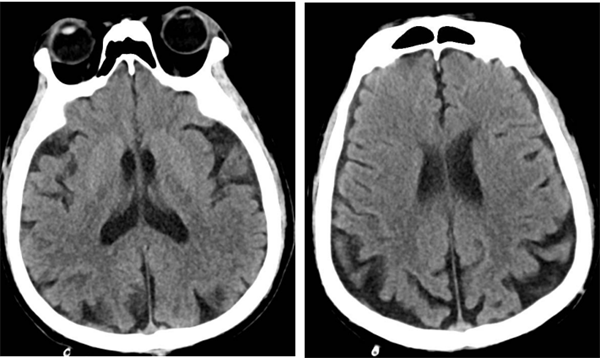

▲术后复查头颅CT

术后,何先生顺利苏醒,回到神经外科病房进行监护治疗,术后7天伤口愈合良好拆线出院。8月何先生来捆绑调教 复查,DSA检查提示右侧颈动脉狭窄已完全恢复并无再狭窄,头晕及左侧肢体乏力症状也完全缓解了。